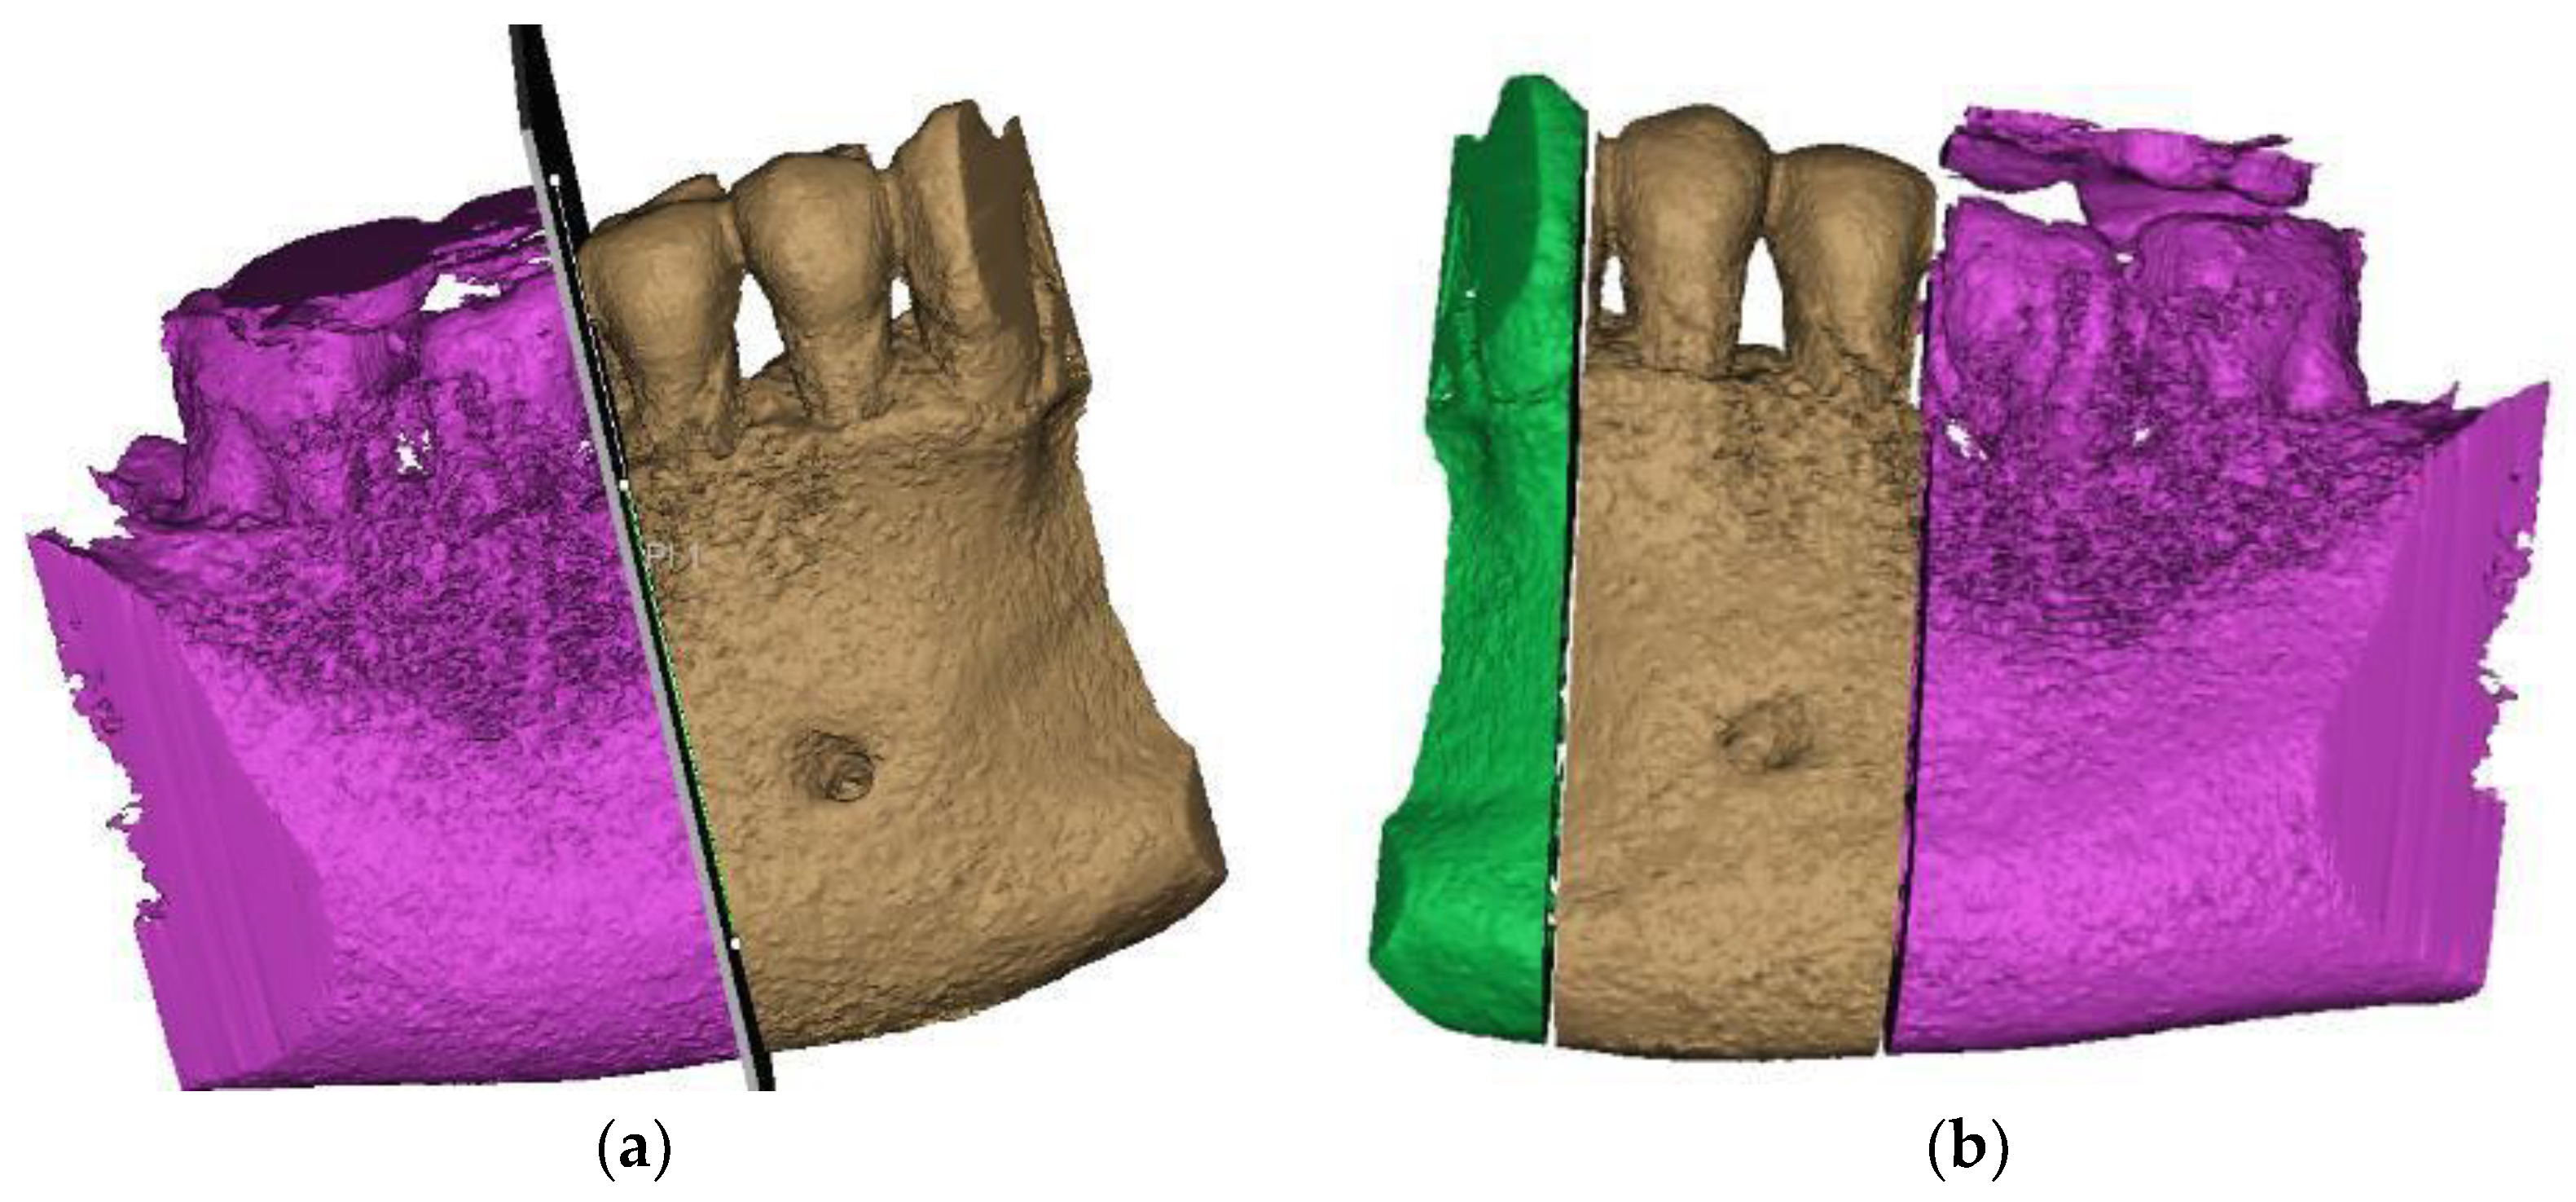

2. Case Description

3. Finite Element Analysis (FEA) of Mandibular Right Premolars